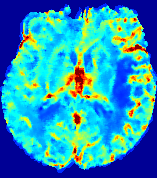

LesionRefer to captionRefer to captionRefer to captionRefer to captionRefer to captionRefer to caption𝐕rgbsubscript𝐕𝑟𝑔𝑏{\bf{V}}_{rgb}Refer to captionRefer to captionRefer to captionRefer to captionRefer to captionRefer to caption𝐕2subscriptnorm𝐕2{\|\bf{V}}\|_{2}Refer to captionRefer to captionRefer to captionRefer to captionRefer to captionRefer to captionRefer to caption3.53.53.52.82.82.82.12.12.11.41.41.40.70.70.70.00.00.0(mm/s)𝑚𝑚𝑠(mm/s)D𝐷DRefer to captionRefer to captionRefer to captionRefer to captionRefer to captionRefer to captionRefer to caption0.0200.0200.0200.0160.0160.0160.0120.0120.0120.0080.0080.0080.0040.0040.0040.0000.0000.000(mm2/s)𝑚superscript𝑚2𝑠(mm^{2}/s)Slice #1Slice #2Slice #3Slice #4Slice #5Slice #6

Figure 4: PIANO feature maps for another patient in the ISLES 2017 training set, where the lesion is located in the right hemisphere. Top row: segmented stroke lesion region (white) on different slices. The corresponding slices for the PIANO feature maps are shown in the following rows.

For a better insight into an estimated velocity field 𝐕𝐕{\bf{V}} and diffusion field 𝐃𝐃{\bf{D}}, we compute the following maps: (1) 𝐕rgbsubscript𝐕𝑟𝑔𝑏{\bf{V}}_{rgb}: Color-coded orientation map of 𝐕=(Vx,Vy,Vz)T𝐕superscriptsuperscript𝑉𝑥superscript𝑉𝑦superscript𝑉𝑧𝑇{\bf{V}}=(V^{x},V^{y},V^{z})^{T}, obtained by normalizing 𝐕𝐕{\bf{V}} to unit length and mapping its 3 components to red, green, blue respectively; (2) 𝐕2subscriptnorm𝐕2\|{\bf{V}}\|_{2}: 222 norm of 𝐕𝐕{\bf{V}}; (3) D𝐷D: scalar field in Eq. 5.

Fig. 3 and Fig. 4 show the PIANO feature maps estimated from two ISLES 2017 patients: all are highly consistent with the lesion in both cases. Details of the blood flow trajectories are revealed in 𝐕rgbsubscript𝐕𝑟𝑔𝑏{\bf{V}}_{rgb} by the ridged patterns and the sharp changes of colors in the unaffected (right) hemisphere, while the flat patterns appearing within the lesion provide little directional information about the velocity and indicate low velocity magnitudes. Velocity magnitudes are more directly visualized via 𝐕2subscriptnorm𝐕2\|{\bf{V}}\|_{2}, from which one can easily locate the lesion where 𝐕2subscriptnorm𝐕2\|{\bf{V}}\|_{2} is low. D𝐷D also indicates lower diffusion values in the lesion, though with less contrast potentially due to the fact that it captures the accumulated effect of CA diffusion at the voxel-level.